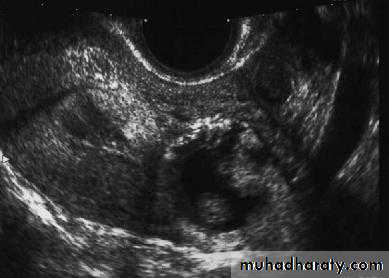

• Transvaginal ultrasound scan (TVS): An intrauterine gestational sac should be visualized at about 4.5 weeks of gestation. The corresponding bHCG at that gestation is around 1500 mIU/ mL. By the time a gestational sac with fetal heart pulsation is detected (at around 5 weeks gestation), bHCG level should be around 3000 mIU/mL.

Thus, if there were discrepancy between the bHCG concentrations and that seen on ultrasound scan (e.g. a high bHCG with no intrauterine pregnancy on ultrasound scan), the differential diagnosis of an ectopic pregnancymust be made.

Identification of an intrauterine pregnancy (gestation sac, yolk sac along with fetal pole) on TVS effectively excludes the possibilityof an ectopic pregnancy in most patients except in those patients with rare heterotopic pregnancy.

The presence of free fluid during TVS is suggestive of a ruptured ectopic pregnancy.